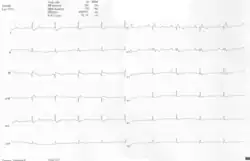

A 12-lead ECG of a woman with Ebstein's anomaly: The ECG shows signs of right atrial enlargement, best seen in V1. Other P waves are broad and tall, these are termed "Himalayan" P waves. Also, a right bundle-branch block pattern and a first-degree atrioventricular block (prolonged PR-interval) due to intra-atrial conduction delay are seen. No evidence of a Kent-bundle is seen in this patient. The T wave inversion in V1-4 and a marked Q wave in III occur; these changes are characteristic for Ebstein's anomaly and do not reflect ischemic ECG changes in this patient.

Other abnormalities that can be seen on the ECG include:

1. signs of right atrial enlargement or tall and broad 'Himalayan' P waves

2. first degree atrioventricular block manifesting as a prolonged PR-interval[7]

3. low amplitude QRS complexes in the right precordial leads

4. atypical right bundle branch block

5. T wave inversion in V1-V4 and Q waves in V1-V4 and II, III and aVF.[8]